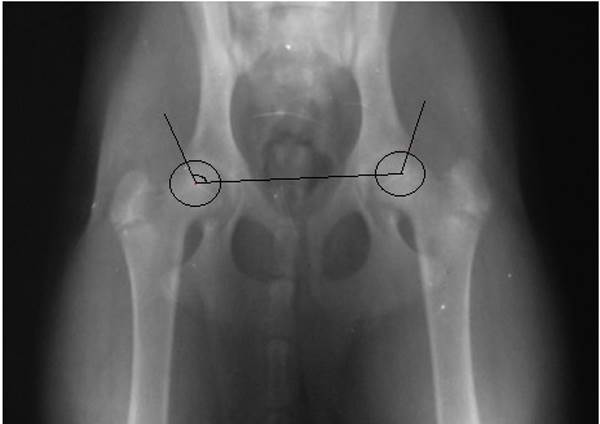

Рентгенограмма тазобедренных суставов выглядит следующим образом:

Параметров, по которым подсчитываются баллы, в классической методике 6, это система Flukiger. Каждый параметр оценивается от 0 до 5 баллов. В основе диагностики лежит определение ряда углов и соотношений в суставе, например, как на рисунке ниже:

1 параметр – угол Норберга, обозначенный на рисунке выше. Параметр оценивается в 0 баллов, если угол Норберга больше или равен 105?.